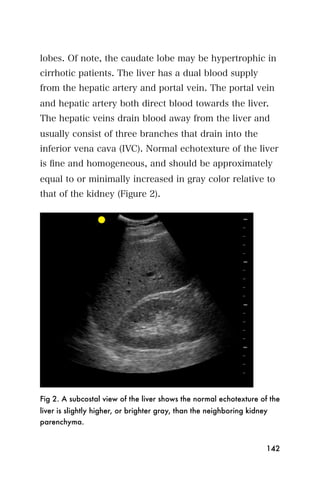

center that is the endometrium.

Figure 3. The bladder (*) and empty uterus (arrow)

An empty uterus may cause the clinician to worry about

an ectopic pregnancy. A ruptured ectopic pregnancy